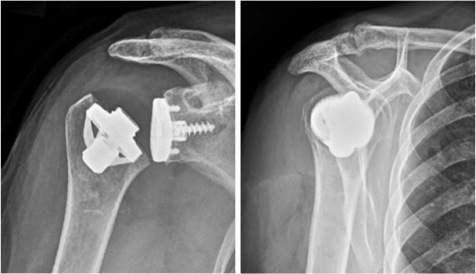

Schaftfreie Lima Schulter-Prothese (re: anatomisch, li: invers), Vorteile: Knochen sparen, bessere Anpassungsmöglichkeit auch bei Deformitäten oder nach Oberarmkopf-Frakturen, sehr gutes Einwachsen durch zementfreie Titan-Verankerung, Konversion einfach

Anatomische schaftfreie zementfreie Schulter-Total-Endoprothese

Inverse schaftfreie zementfreie Schulter-Total-Endoprothese